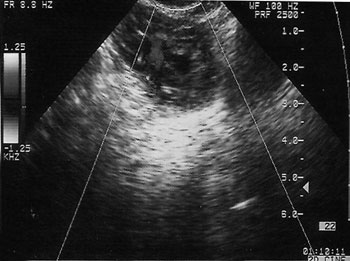

Εικόνα 2. Διακολπικός υπερηχογραφικός

έλεγχος έκτοπης κύησης.

Το διακολπικό υπερηχογράφημα είναι ευρέως αποδεκτό ως η καλύτερη επιλογή, έναντι

του διακοιλιακού στη διάγνωση της έκτοπης κύησης.(11) Το διακοιλιακό υπερηχογράφημα

κοιλότητα, έξω από την εμβέλεια της ενδοκολπικής κεφαλής.(8-11) Επίσης, το διακολπικό

υπερηχογράφημα απαιτεί λιγότερο χρόνο αναμονής πριν την εξέταση, ενώ παρέχει

μια εικόνα της πυέλου σε υψηλότερη ανάλυση, προσφέροντας πρόσθετες ανατομικές

πληροφορίες.(12-14)

Η υψηλής ανάλυσης εικόνα της διακολπικής κεφαλής προσφέρει καλύτερη εικόνα της

ενδομήτριας κοιλότητας, των εξαρτημάτων και των ωοθηκών. Το διακολπικό υπερηχογράφημα

αποκαλύπτει την ενδομήτρια κύηση μια εβδομάδα νωρίτερα, έναντι της διακοιλιακής

προσέγγισης. Πράγματι, μερικές μελέτες έχουν δείξει ότι το κύριο σημείο στο

οποίο υπερτερεί το διακολπικό υπερηχογράφημα έναντι του διακοιλιακού, είναι

ο πιο ακριβής προσδιορισμός των ενδομήτριων, παρά των έκτοπων ευρημάτων.